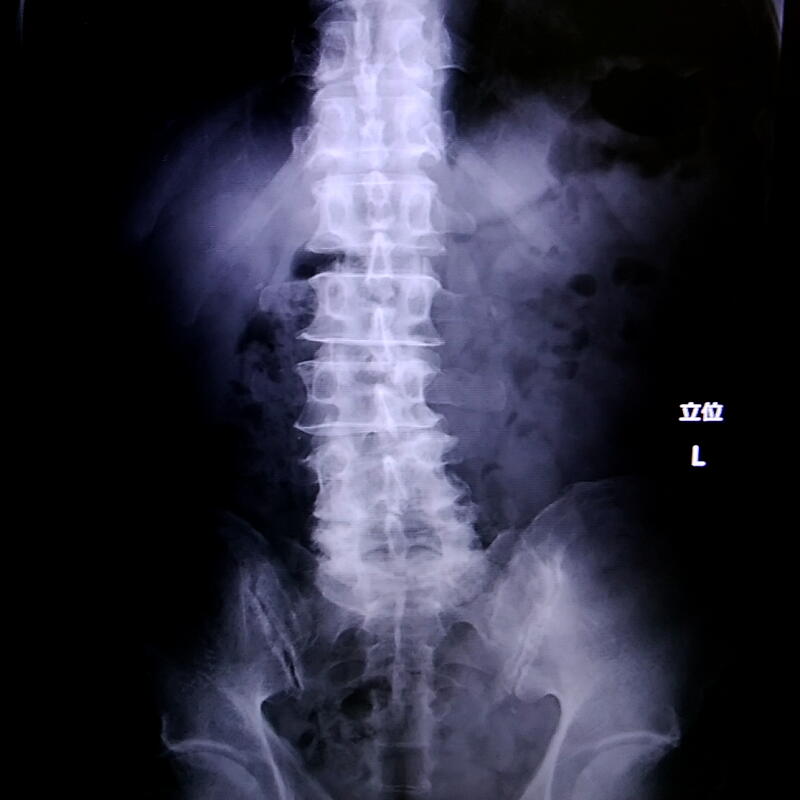

そしてレントゲンを撮った結果「腰椎変形症」という診断が下された。

加齢に伴う腰痛の多くは「腰椎すべり症」と言って腰椎が前後方向にずれるらしいのだけど、私の場合横方向にずれてしまっている。

私としてはこの坐骨神経痛の痛みとずっと付き合うのは勘弁してほしかったので、手術で治るものならすぐにでも手術してほしいと訴えたのだけど、リスクの大きいオペになるのでとりあえずは保存療法で様子を見ましょう、ということになった。